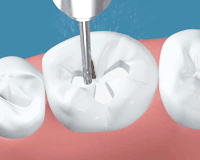

切削器具でむし歯の部分を選択的に削ります

完全にむし歯を取り終えたところです。かなり大きな穴が開いています。

削った表面に対して接着処理を行います。

ここが重要ですが、緊密にかつスムーズに詰められるように壁をつくって余計なところに流れないよう堰き止めます。この壁を作る器具の出現で、型採りが必要なレジンインレーは全く行わないようになりました。

プラズマ照射器・高出力ハロゲン照射

レジンを緊密に充填し、専用の光で確実に硬化させます。

形態修正やかみ合わせの調整を行い、表面を研磨します。